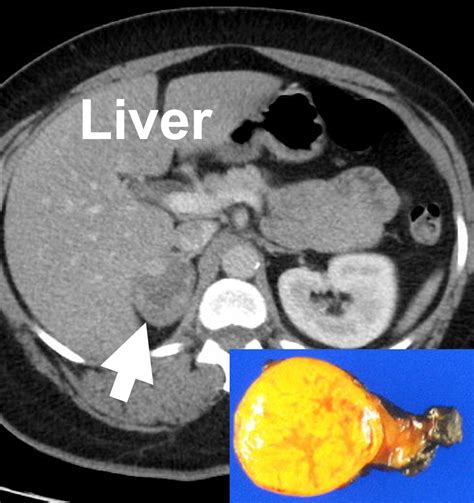

• Imaging Review: A radiologist will analyze the "washout" characteristics of the nodule on a CT scan to estimate the lipid content within the tissue.

Differentiating Between Benign and Malignant Nodules

Differentiating between a harmless adenoma and a malignant tumor is the primary objective of your medical team. Benign adrenal adenomas are the most frequent finding. These are generally small, stable over time, and lipid-rich. Conversely, adrenocortical carcinoma is a rare form of cancer that usually presents as a larger, irregularly shaped mass. Imaging techniques such as contrast-enhanced CT scans, MRI, or even PET scans may be utilized if the initial findings are inconclusive or if the nodule demonstrates suspicious features.